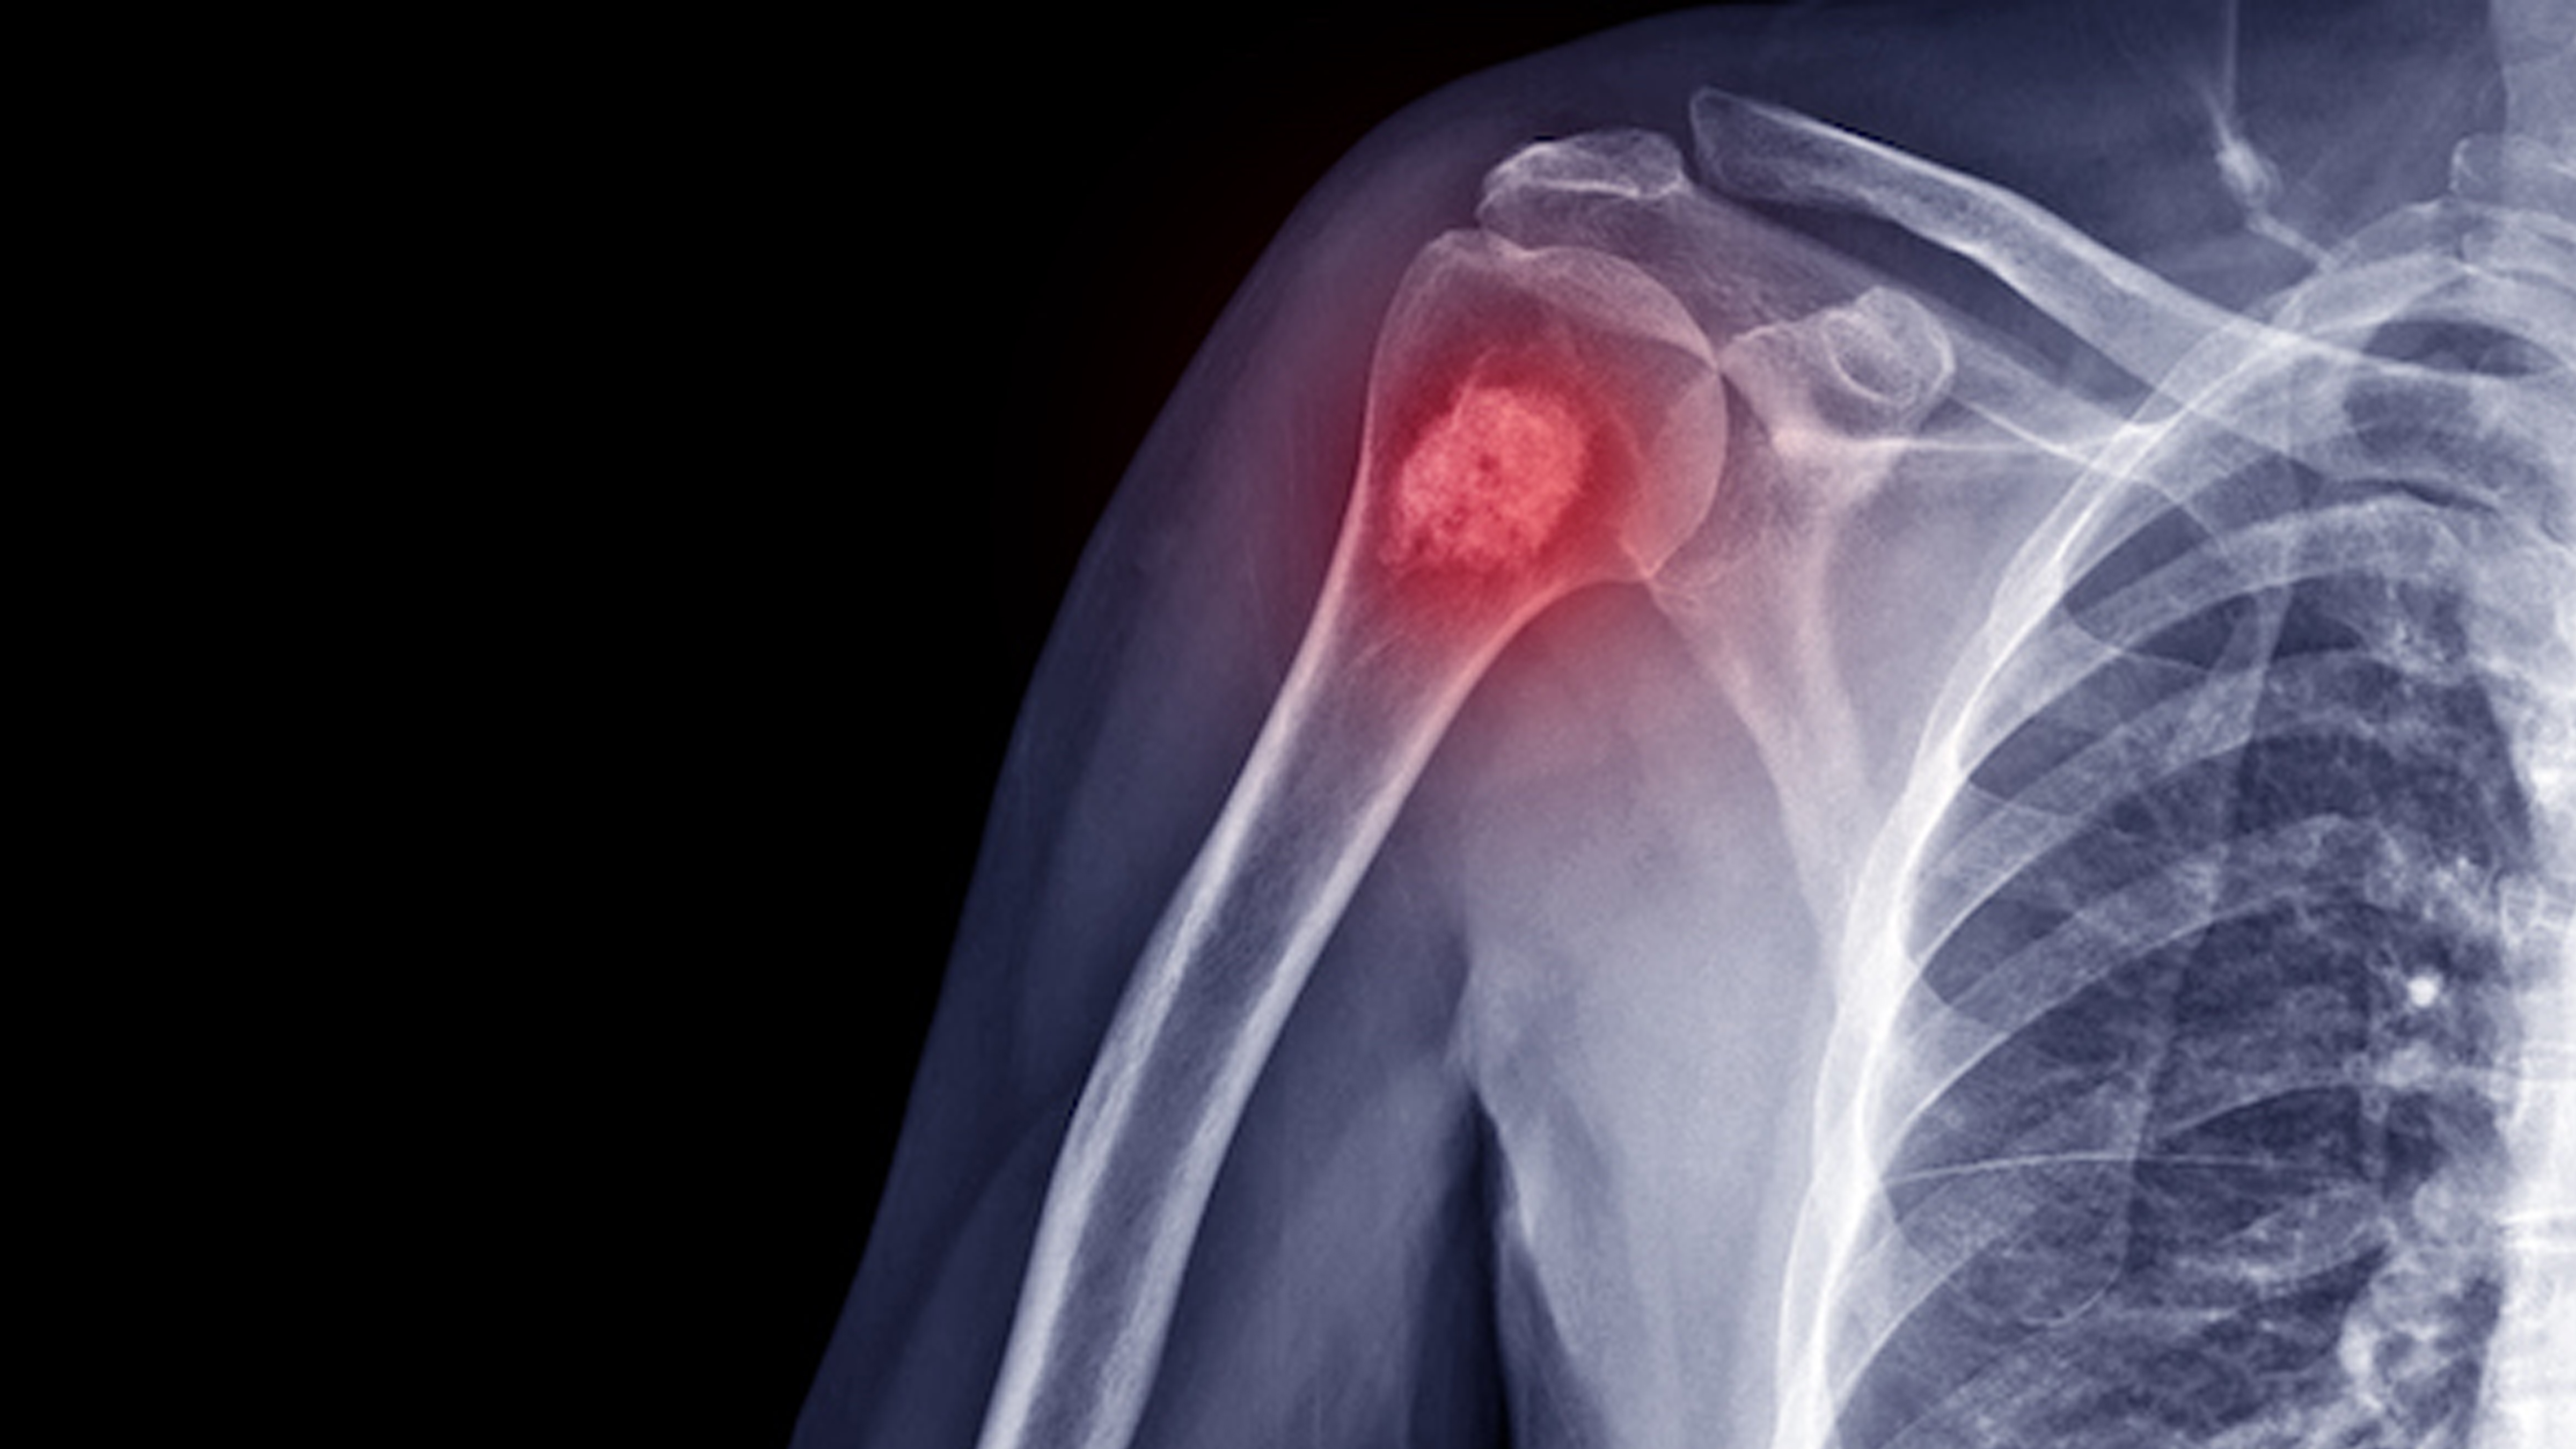

🦴 Orthopedic Oncology in Dubai

Expert Care for Bone & Soft Tissue Tumors

Orthopedic Oncology is a specialized field of orthopedic surgery focused on the diagnosis and treatment of bone and soft tissue tumors. At Subhash Ortho Clinic, Dubai, under the expert care of Dr. Subhash Ushakoyala, we provide comprehensive care for patients with benign and malignant musculoskeletal tumors.

Bone and soft tissue tumors can be benign (non-cancerous) or malignant (cancerous). Early diagnosis and treatment are essential for preserving limb function, preventing spread, and improving quality of life. We offer both surgical and non-surgical treatments tailored to each case.